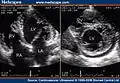

Trabeculation of the ventricles is normal, as are prominent, discrete muscular bundles greater than 2mm. In non-compaction there are excessively prominent trabeculations. Echocardiography is the reference standard for diagnosing NCC, although it can be well defined by computer tomography scan, positron emission tomography and magnetic resonance imaging.[13] Chin, et al., described echocardiographic method to distinguish non-compaction from normal trabeculation. They described a ratio of the distance from the trough and peak, of the trabeculations, to the epicardial surface.[14] Non-compaction is diagnosed when the trabeculations are more than twice the thickness of the underlying ventricular wall.

Transthoracic two-dimensional echocardiogram in apical four chamber and parasternal short axis at the level of both ventricles demonstrate dilatation, deep trabeculae and intertrabecular recesses in the inferior, lateral, anterior walls, middle and apical portions of the septum and apex of the left ventricle.